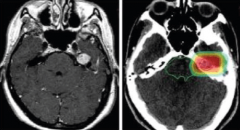

大脑镰旁脑膜瘤手术难点

大脑镰旁脑膜瘤是一种常见的脑膜瘤位于大脑纵裂,源自大脑镰...